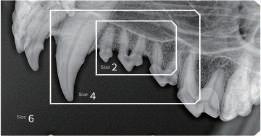

Our sensors feature a fiber optic plate that enhances clarity, safety, and durability by filtering residual X-rays. Their wide dynamic range delivers sharp imaging at any dose, simplifying image capture. Size 1.3 matches the average 22.5 mm molar length, overcoming the limitations of conventional Size 1. Size 4 meets the growing demand in veterinary care, filling a critical void in animal healthcare and opening opportunities in an underserved market.